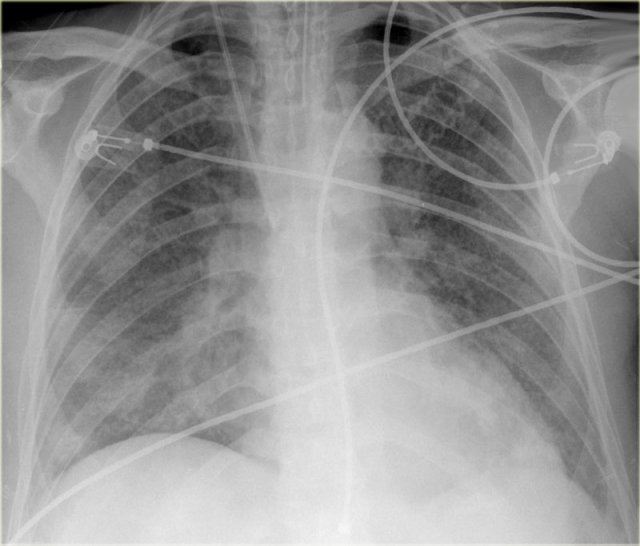

Increased CTR due to pericardial effusion Increased CTR due to pericardial effusion

On the left a patient, who recently underwent a valve replacement.

There is a large cardiac silhouette, which could be the result of cardiomegaly.

Because of the recent cardiac surgery, the possibility of pericardial effusion was taken into account, which is nicely demonstrated on the CT-image.

On the left another patient with a large cardiac silhouette on the chest x-ray due to pericardial effusion.

Pericardial effusion is demonstrated on the coronal CT-reconstruction.